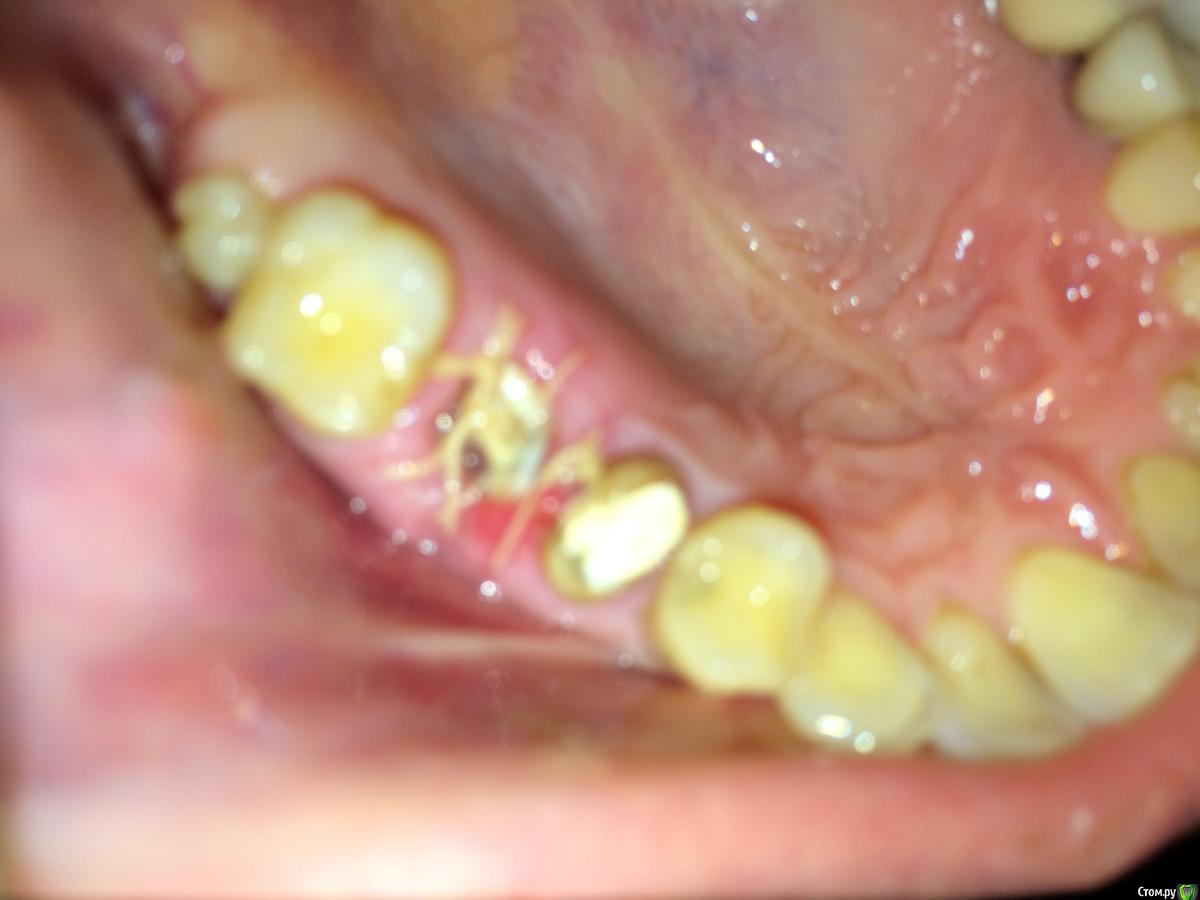

foringella Опубликовано 19 апреля, 2016 Поделиться Опубликовано 19 апреля, 2016 (изменено) Подскажите, пожалуйста, что делать с воспаленной десной? сегодня 5-й день после сложного удаления (рассверлили на 3 части, зуб крошился). Извините за качество, лучше сделать не получается. P.S. До удаления стояла сдвоенная коронка на 2.5. и 2.6. Перед удалением ее распилили, оставив острые края. Хирург 2.5 удалять не стал, несмотря на то, что под коронкой на нем приличный кариес. С момента удаления болела десна. Думала из-за острых краев коронки. Вчера коронку удалили, просто постучав по ней "зубилом" - она отвалилась. Сегодня десна еще краснее стала и постоянно болит. Изменено 19 апреля, 2016 пользователем foringella Ссылка на комментарий

foringella Опубликовано 9 мая, 2016 Автор Поделиться Опубликовано 9 мая, 2016 На очном осмотре врач признала, что воспаление есть, положила лекарство.Десна заживала долго, приходилось мазать санагелем. На сегодня вопрос в следующем: беспокоит острый край в десне не знаю чего (кортикальная пластинка, наверно, называется).Знающие люди, подскажите, пожалуйста что с этим делать? Является ли это последствием неправильных действий при удалении?http://s03.radikal.ru/i176/1605/4e/794706377626.jpg Ссылка на комментарий

Doctor Vlad Опубликовано 9 мая, 2016 Поделиться Опубликовано 9 мая, 2016 скорей острый край альвеолы что не является косяком доктора. но снимок покажет, если нет доверия... 1 Ссылка на комментарий

foringella Опубликовано 10 мая, 2016 Автор Поделиться Опубликовано 10 мая, 2016 Спасибо всем откликнувшимся! снимок я сделала после удаления - по снимку все ок.Насчет острого края альвеолы - пойду к врачу для устранения проблемы, зубы чистить мешает, болит при прикосновении. Ссылка на комментарий